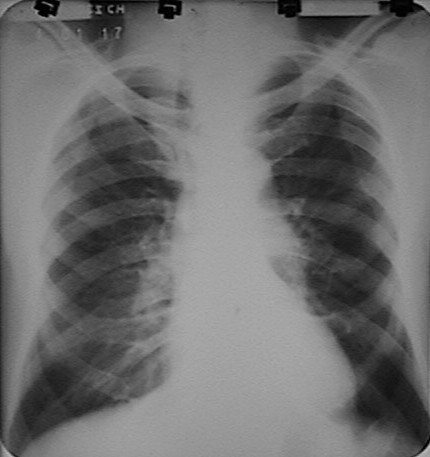

Fig.11.

28 años. APP:  parto  hace 4 meses. MC: dolor torácico izquierdo. Síndrome febril

desde hace 9 días.Tratamiento con Penicilina. Leuco. 25x 109, Poli 85.

US:

Gran tumoración ecogénica, heterogénea con derrame pericárdico acompañante.

Tórax: Opacidad densa y homogénea, de contornos

regulares y bien definidos que ensancha marcadamente el

mediastino

en el lado izquierdo en relación con gran tumoración.

No se observan calcificaciones en su interior. Marcador sobre el vértice

derecho. No se aprecia lesión ósea. |